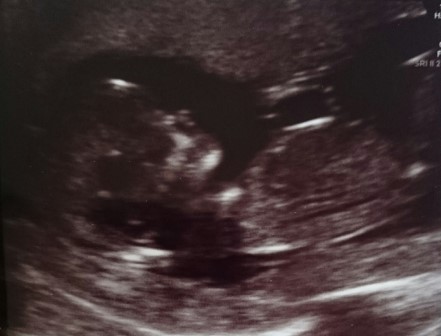

Really. Tbh the pictures aren't nearly as clear as we had hoped as you could really see the nub on the screen. There is this one too...

Ok there's the nub :) girl!

*UPDATE * Booked a last minute gender scan and it is a boy